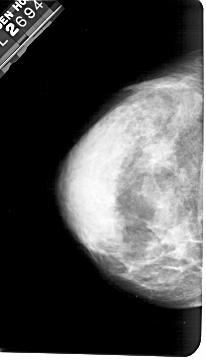

A_1185_1.LEFT_CC

LEFT_CC LINES 5401 PIXELS_PER_LINE 3076 BITS_PER_PIXEL 12 RESOLUTION 43.5 NON_OVERLAY